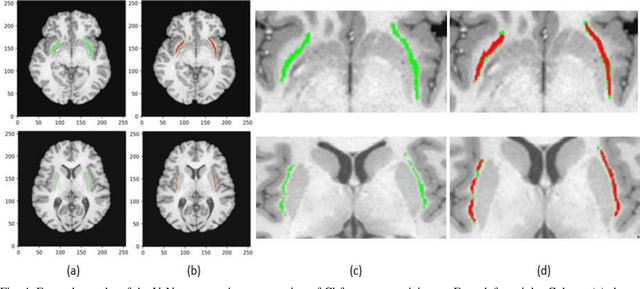

In recent years, Deep Learning (DL) has shown promising results in conducting AI tasks such as computer vision and image segmentation. Specifically, Convolutional Neural Network (CNN) models in DL have been applied to prevention,detection, and diagnosis in predictive medicine. Image segmentation plays a significant role in disease detection and prevention.However, there are enormous challenges in performing DL-based automatic segmentation due to the nature of medical images such as heterogeneous modalities and formats, insufficient labeled training data, and the high-class imbalance in the labeled data. Furthermore, automating segmentation of medical images,like magnetic resonance images (MRI), becomes a challenging task. The need for automated segmentation or annotation is what motivates our work. In this paper, we propose a fully automated approach that aims to segment the human claustrum for analytical purposes. We applied a U-Net CNN model to segment the claustrum (Cl) from a MRI dataset. With this approach, we have achieved an average Dice per case score of 0.72 for Cl segmentation, with K=5 for cross-validation. The expert in the medical domain also evaluates these results.